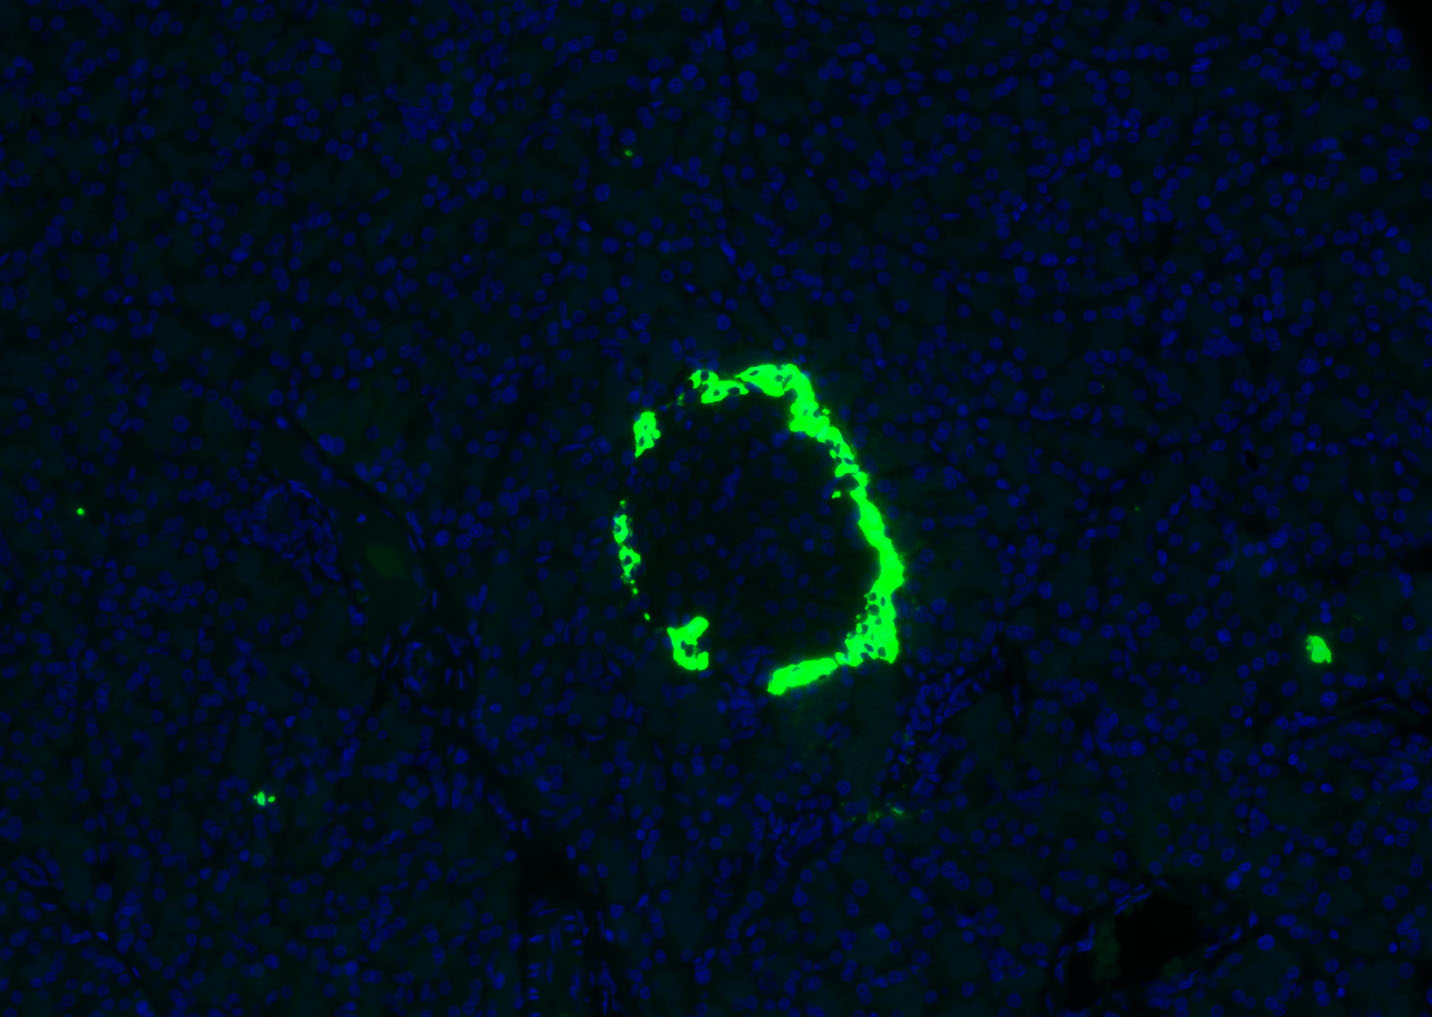

| 产品应用 | IHC-P=1:100-500, IHC-F=1:100-500, IF=1:100-500 Not yet tested in other applications. |

| {IHC-P} | {1:100-500} |

| {IHC-F} | {1:100-500} |

| {IF} | {1:100-500} |

[IF={{ 3.738 }}] {Tong Su. et al. MiR-34a-5p and miR-452-5p: The Novel Regulators of Pancreatic Endocrine Dysfunction in Diabetic Zucker Rats?. Int J Med Sci. 2021; 18(14): 3171–3181} {IF} {Rat}

We demonstrate below a double immunostaining using a pair of rabbit antibodies to glucagon (amplified at a dilution of 1:5000 on path 12) and neurofilament M (conventionally stained at a dilution of 1:2000 on path 1) in a section of non-perfused rat pancreas